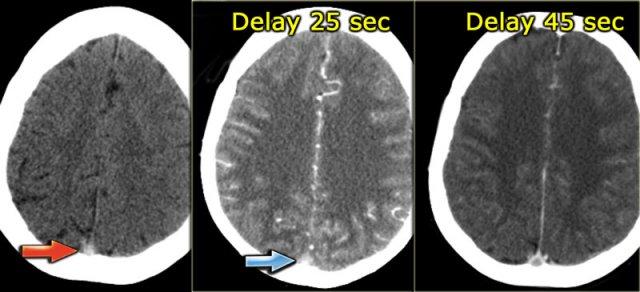

Bên trái là ba hình ảnh của một bệnh nhân có huyết khối tĩnh mạch tại xoang dọc trên.

Ở hình ngoài cùng bên trái, chúng ta thấy dấu hiệu mạch máu tăng tỷ trọng trên CT không tiêm thuốc cản quang.

Hình ở giữa được chụp 25 giây sau khi bắt đầu tiêm thuốc cản quang.

Có hình ảnh ngấm thuốc động mạch và trông như thể xoang dọc trên cũng đang ngấm thuốc, nhưng thực chất đây là hiện tượng “xuyên sáng” (shine through) của cục huyết khối tăng tỷ trọng.

Chỉ đến hình ảnh bên phải, được chụp 45 giây sau khi tiêm thuốc cản quang, mới xuất hiện dấu hiệu delta rỗng, xác nhận sự hiện diện của huyết khối trong xoang.